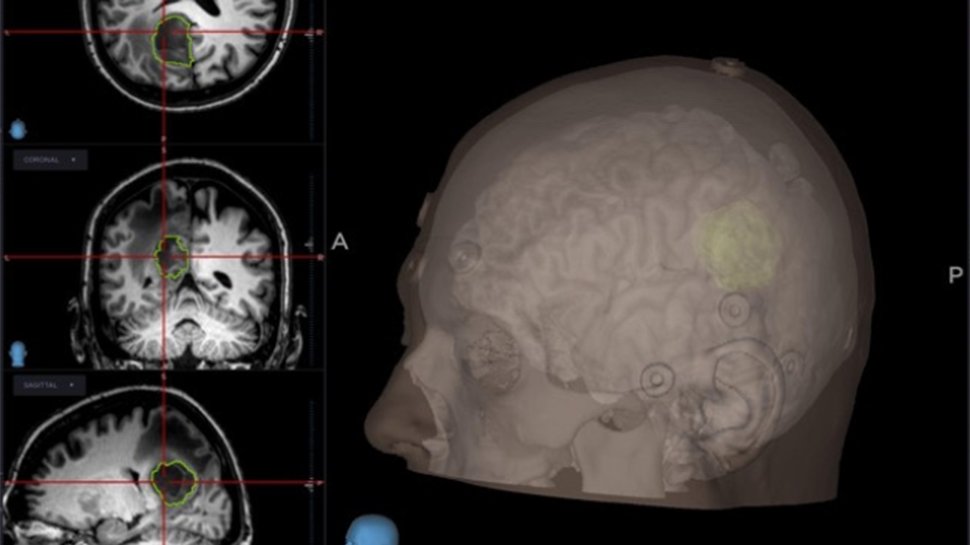

La neurocirugía craneal es una subespecialidad altamente compleja enfocada en el tratamiento de patologías intracraneales, incluyendo tumores cerebrales, traumatismos, malformaciones vasculares y alteraciones estructurales del sistema nervioso central.

Cada procedimiento requiere una planificación meticulosa basada en estudios de imagen avanzados, con el objetivo de intervenir de manera precisa y segura, minimizando riesgos y preservando la función neurológica del paciente.

Se emplean técnicas quirúrgicas modernas, apoyadas en tecnología de alta precisión, que permiten abordajes más controlados y resultados clínicos más favorables.